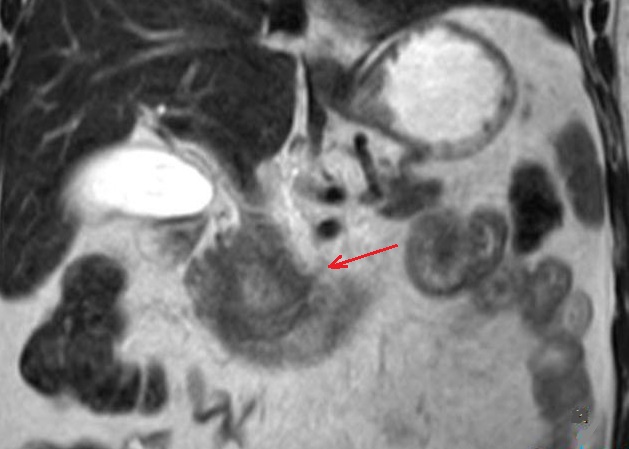

Aspect lesionaire d'une

adenocarcinoma cephalique du pancreas . Le tumeur

est en globulaitre , a bord peu nette et legerement a

hypointense plus que le parenchyme saint du pancreas .

Image radiologique IRM ponderee T1 Fat Sat en coupe

axial |

|

Une autre cas de

adenocarcinoma du pancreas ponderee sur T2 . Image

radiologique du tumeur est hyposignal avec

image de contenue heterogene hypersignal (

fleche rouge ) |